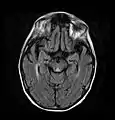

Axial MRI FLAIR image showing hyperintense signal in the mesial dorsal thalami, a common finding in Wernicke encephalopathy. This patient was nearly in coma when IV thiamine was started, he responded moderately well but was left with some Korsakoff type deficits.